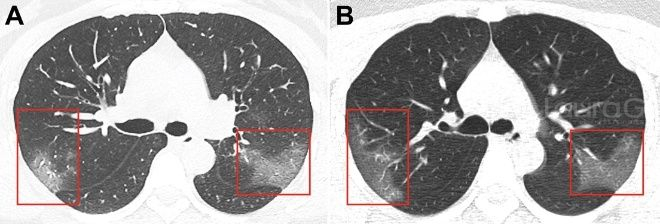

Las imágenes de sus pulmones mostraban manchas blancas que son denominadas como opacidad de vidrio esmerilado, algo muy parecido a la neumonía.

En la fotografía A, es la mujer al ser recién diagnosticada y la imagen B, fue tomada luego de tres días de la infección. Los médicos se han sorprendido, ya que estas corresponden a una persona enferma de neumonía, la cual tiene líquidos en los pulmones.